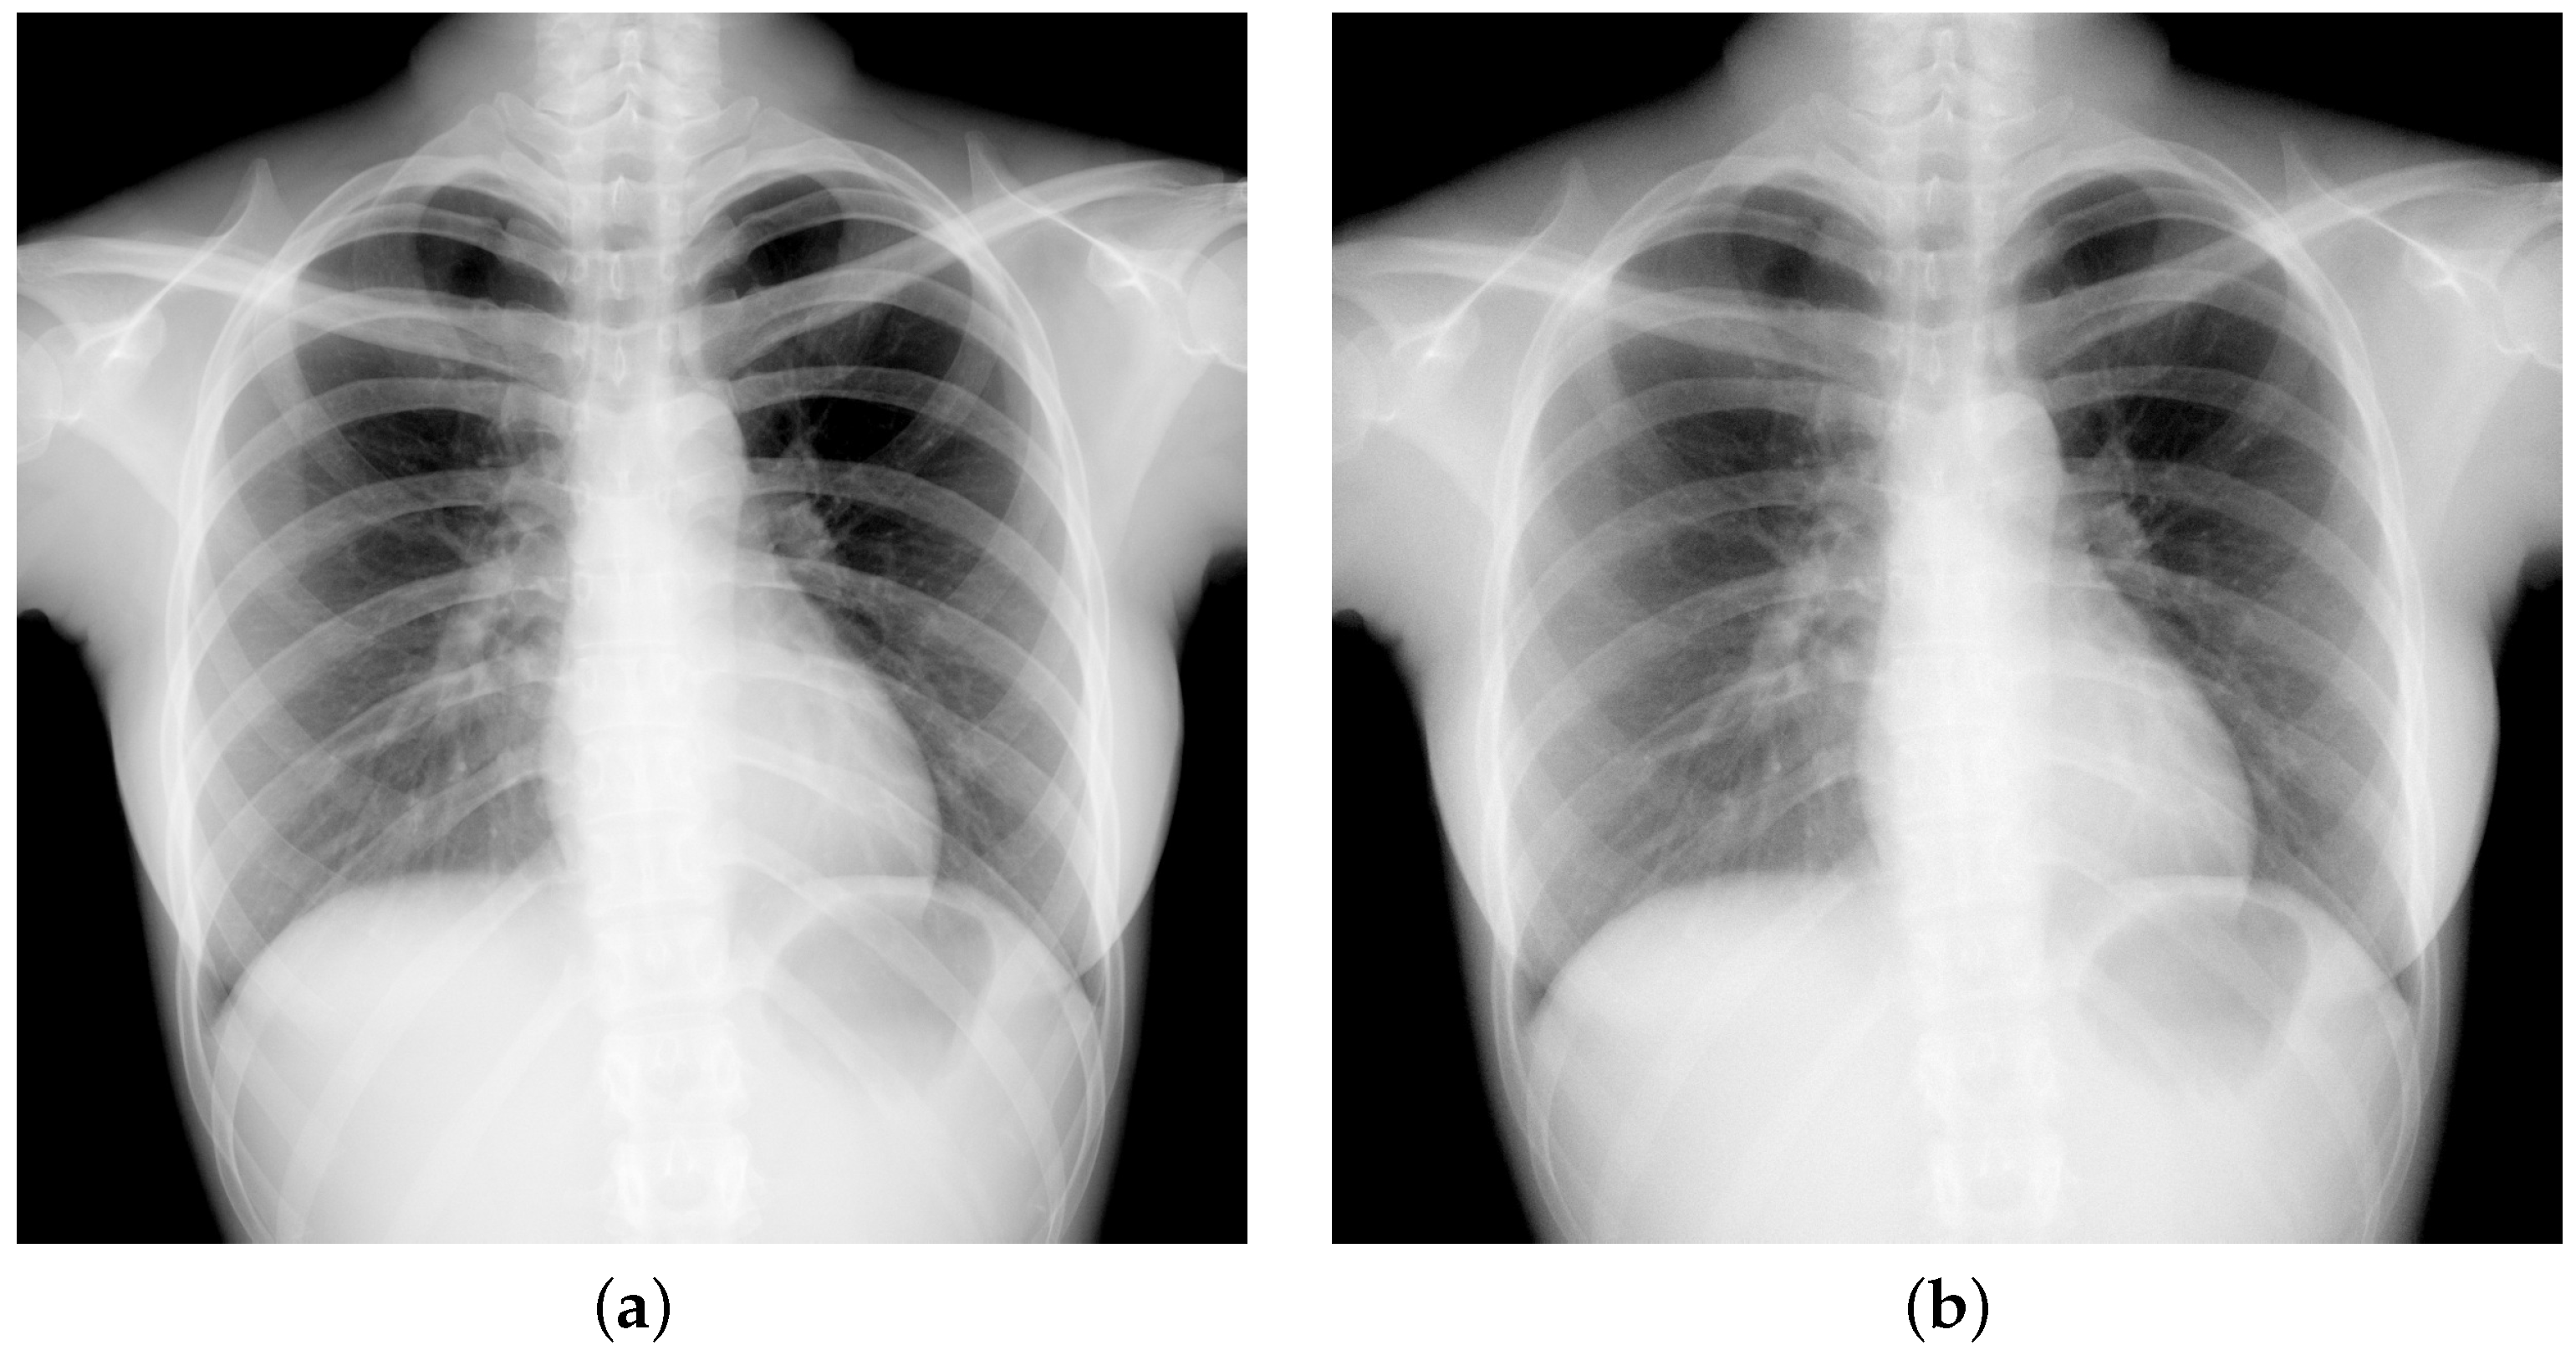

4.2. Low-Dose Radiography Imaging